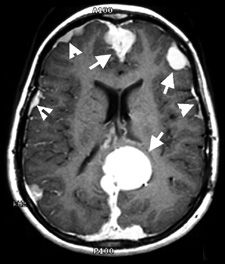

- اسکن توموگرافی کامپیوتری (سی تی اسکن)

- تصویربرداری رزونانس مغناطیسی (MRI)

این بیماران نیاز به ارزیابی شنوایی خود دارند. ارزیابی چشمپزشکی، MRI، شنواییسنجی و تست پتانسیل تحریکی ساقه مغز در مدیریت این بیماری مهم است. هنوز هم جراحی درمان ترجیحی برای تومورهای علامتدار است. اما میزان عود این تومورها ۴۴ درصد است. میتوان از پرتودرمانی استفاده کرد، اما خطر بدخیم شدن تورمورها افزایش مییابد.

بیماران مشکوک به نوروفیبروماتوز نوع ۲ باید MRI سر و ستون فقرات انجام دهند. ایجاد برشهای نازک از طریق کانالهای شنوایی داخلی مهم است. اگر تومور روی ساقهی مغز فشار میآورد یا از کاهش شنوایی جلوگیری میکند، درمان انجام میشود.